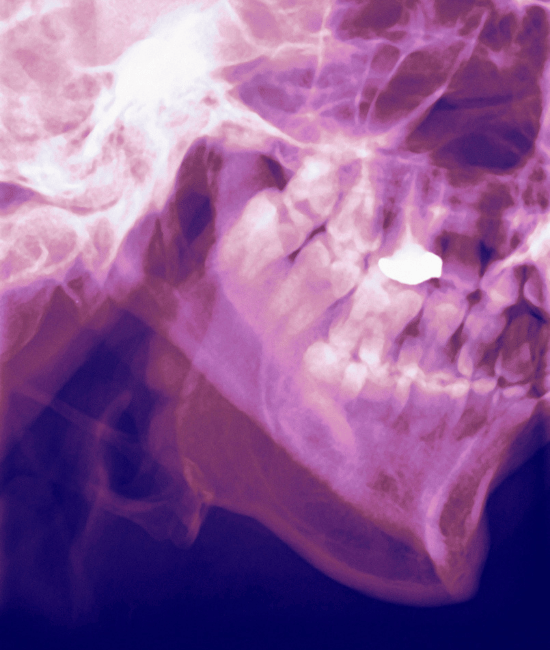

Your temporomandibular joint (TMJ) connects your lower jaw (mandible) to the temporal bone of the skull and allows you to chew, yawn, and speak. The TMJ structure is essential for proper function, and the joint works in coordination with the muscles that control jaw movement, including the chewing muscles. There are two temporomandibular joints, one on each side of your head.

When this joint or the surrounding muscles become irritated, it can lead to temporomandibular disorder (TMD), which encompasses a range of temporomandibular joint disorders.